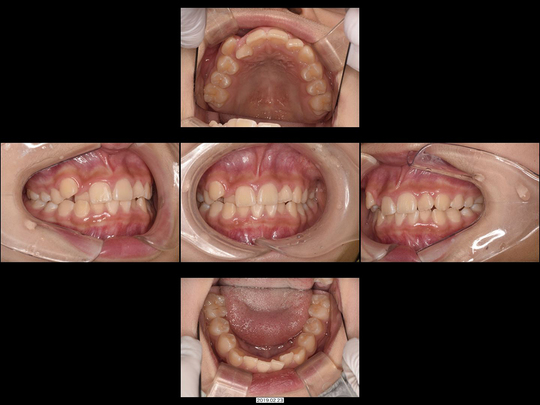

矯正前

画像をクリックで拡大

矯正後

治療の説明

抜歯した後「入れ歯以外なら歯を削ってブリッジかインプラントにするしかない」と診断されたケースです。

精査の結果、CT画像で見るだけでもインプラント治療は非常に困難だと分かりました。ブリッジを選択した場合は両サイドの歯の削る量が大きすぎるため、事前に神経を抜かないと対応が困難です。20代前半という年齢、高齢になってもメインテナンスしやすいのは自分の歯だけであることなどを考慮し、矯正治療を選択。表側の矯正装置にて上下の歯並び・咬み合わせを整えました。

治療の期間・回数

30か月、30回

​費用

990,000円